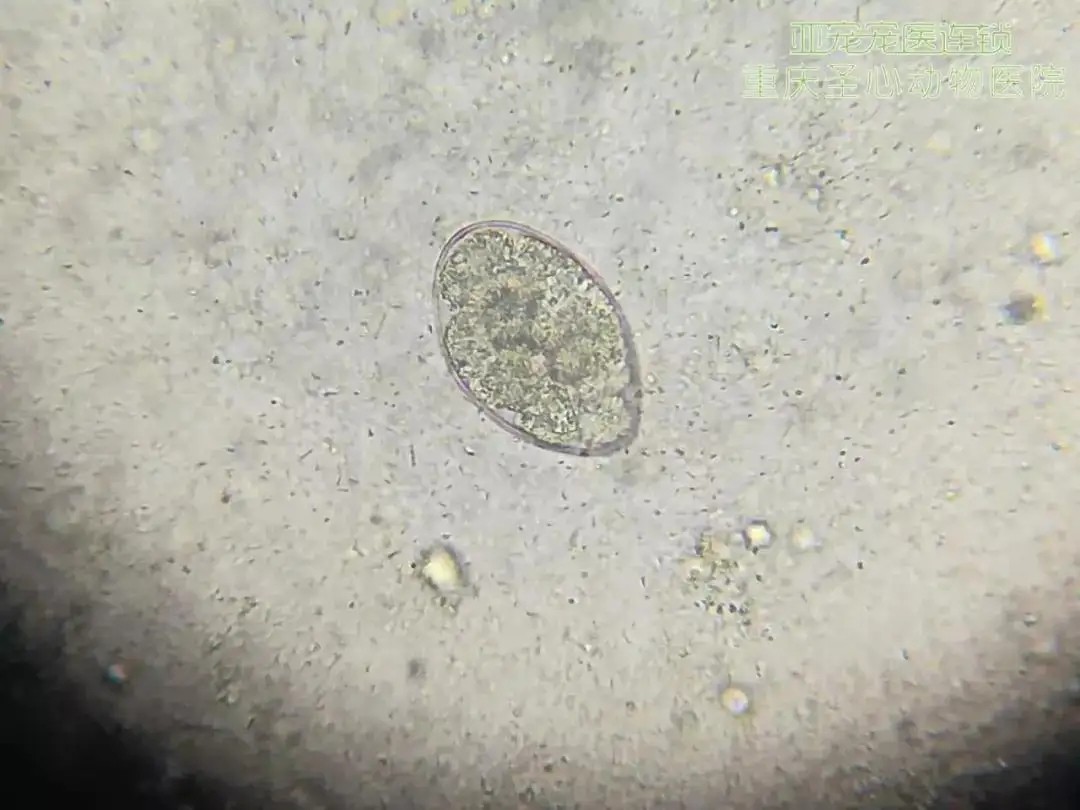

但有机肥往往存在大量害虫及虫卵、有害微生物,直接使用,容易形成病害侵染,严重危害农作物。另外,大型养殖场产生的畜禽排泄物,往往含有大量抗生素残留物,植物残体内含难以降解的纤维素、半纤维素、木质素物质,农作物难以直接吸收利用,直接使用“生肥”会影响植物根系在土壤中生长,长期堆积还容易滋生病虫害。

另外,现代畜禽养殖过程中大量使用抗生素防治病害,畜禽排泄物含有大量抗生素残留物,堆肥中产生的丰富微生物和70℃以上高温,可有效降解抗生素残留物,同时杀死害虫和虫卵,杀灭杀死有害细菌、真菌,钝化部分重金属离子。